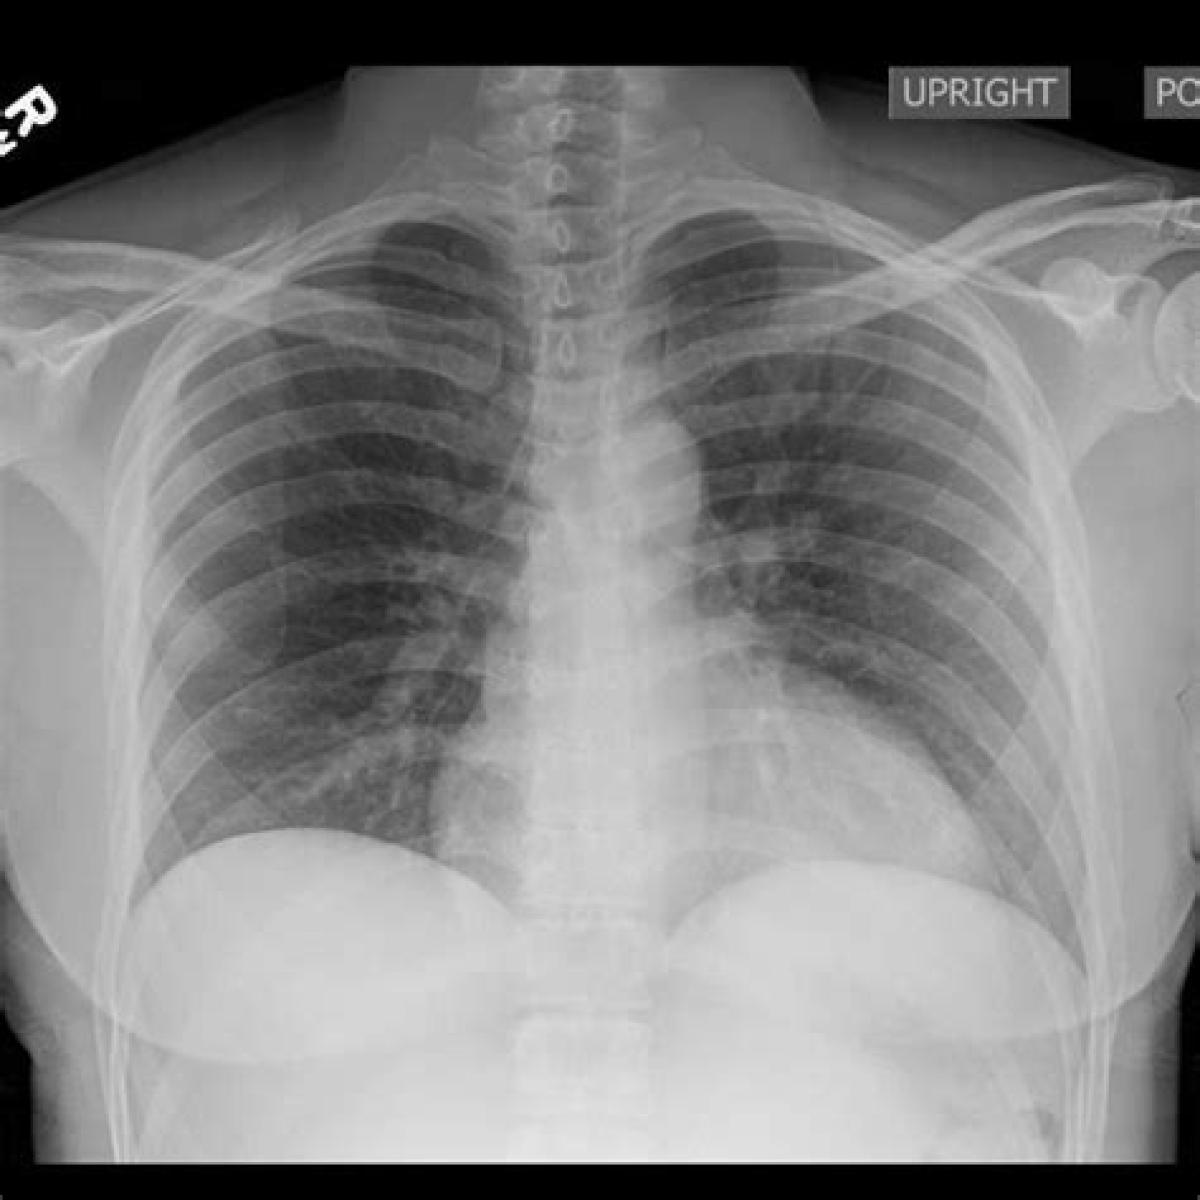

این رادیوگرافی نمای خلفی قدامی (PA) قفسه سینه است یعنی برای گرفتن آن کلیشه رادیوگرافی در جلوی قفسه سینه قرار گرفته و امواج اشعه ایکس از پشت تابیده می‌شود و بیمار ایستاده است.

البته در موارد خاص ممکن است بیمار دراز کشیده باشد یا گاه نمای جانبی قفسه سینه درخواست می‌شود ولی نمای استاندارد رادیوگرافی قفسه سینه خلفی قدامی در بیمار ایستاده است.